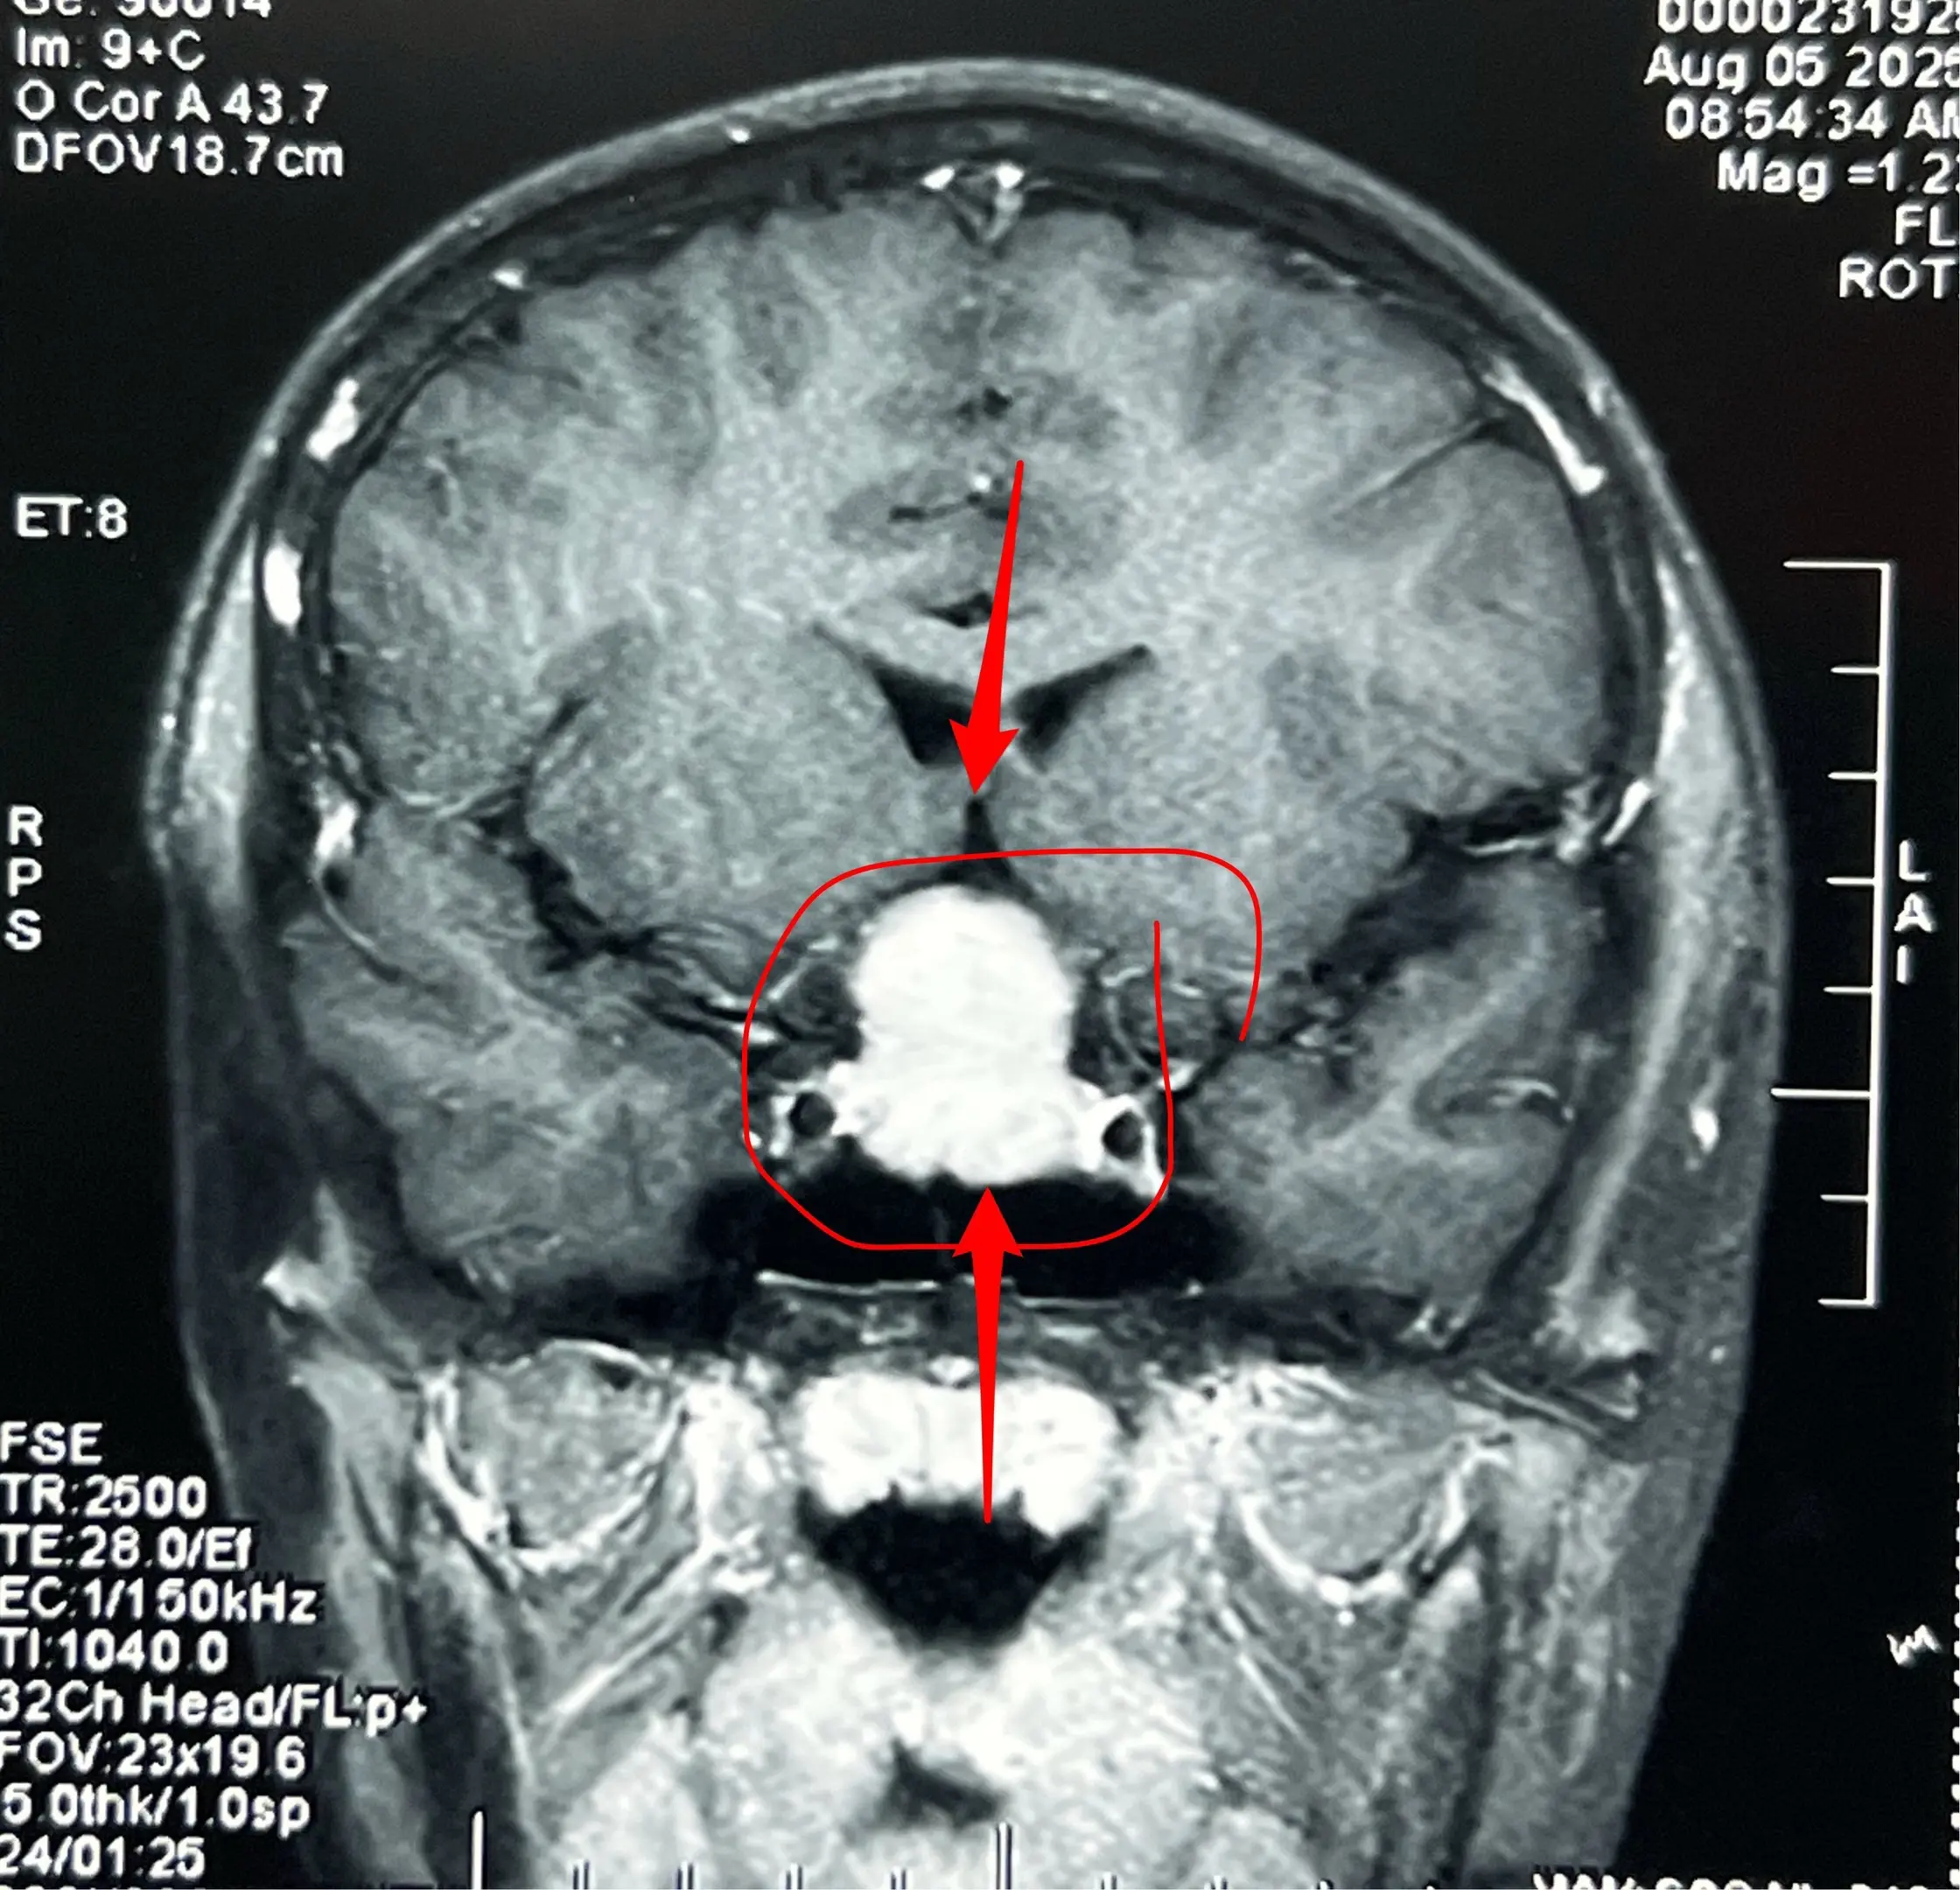

12岁男孩子,视力差、身高增长缓慢。12岁男孩子,视力下降、身高增长缓慢。头CT及MRI显示为典型的造釉型颅咽管瘤。2025年8月7日作了开颅手术。 根据术前的CT和MRI无法判断出垂体受压程度、能否保留垂体和垂体柄。 手术中发现垂体受肿瘤压迫成薄片状,如同饺子皮。好在肿瘤与垂体粘连不紧,经过细心分离,将肿瘤完全切除,同时垂体柄-垂体保留约90%(垂体前叶和后叶均保留)。 这样保留垂体柄和垂体是有意义的,可以减少垂体危象的发生。